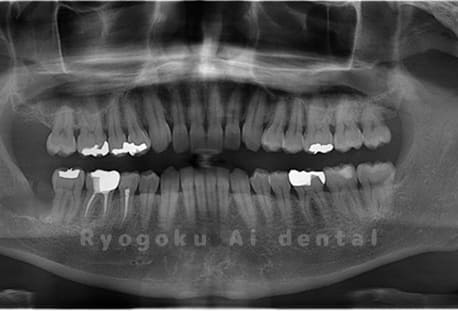

Case04

- 原因

- 上顎の親知らず、下顎の水平埋伏の親知らず

- 治療内容

- 上顎の親知らず、下顎の水平埋伏の親知らずを抜歯したケースです。

<リスク・副作用>

手術後は痛み、腫れ、痺れなどの副作用が生じる場合があります。